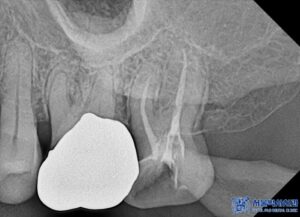

임플란트 치료 외에도, 환자분의 남아있는

치아들 중 심한 충치가 있는 어금니

(오른쪽 위 큰 어금니, 왼쪽 위 작은 어금니,

왼쪽 위 큰 어금니, 왼쪽 아래 큰 어금니)는

신경치료를 진행하였습니다.

특히, 신경치료 시 일반적인 충전재(고무) 대신

MTA 신경치료를 적용하였습니다.

신경치료가 끝난 어금니는 치아를 보호하기 위해

크라운 치료를 진행하였습니다.